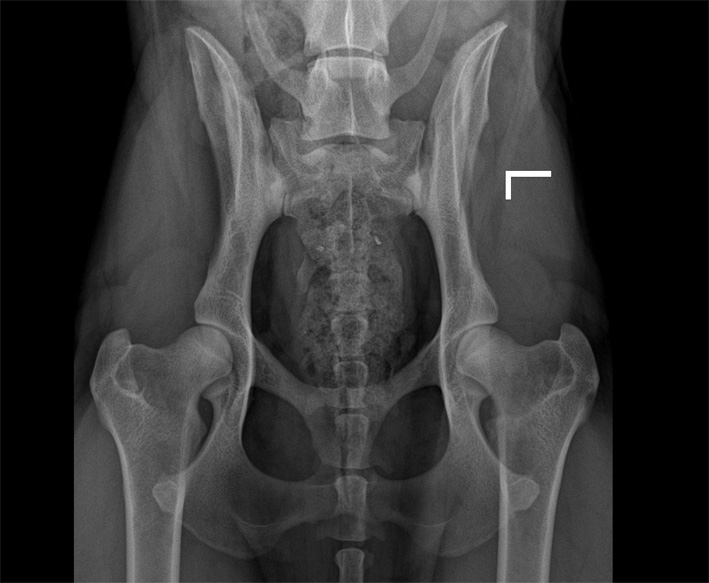

Hier nun einige HD Röntgenbilder:

HD frei / HD- A / HD-0 / HD-normal |

= HD-frei |

HD-0 |

normal |

Normal, unauffällige Gelenke, NORBERG-Winkel von 105 Grad oder mehr |